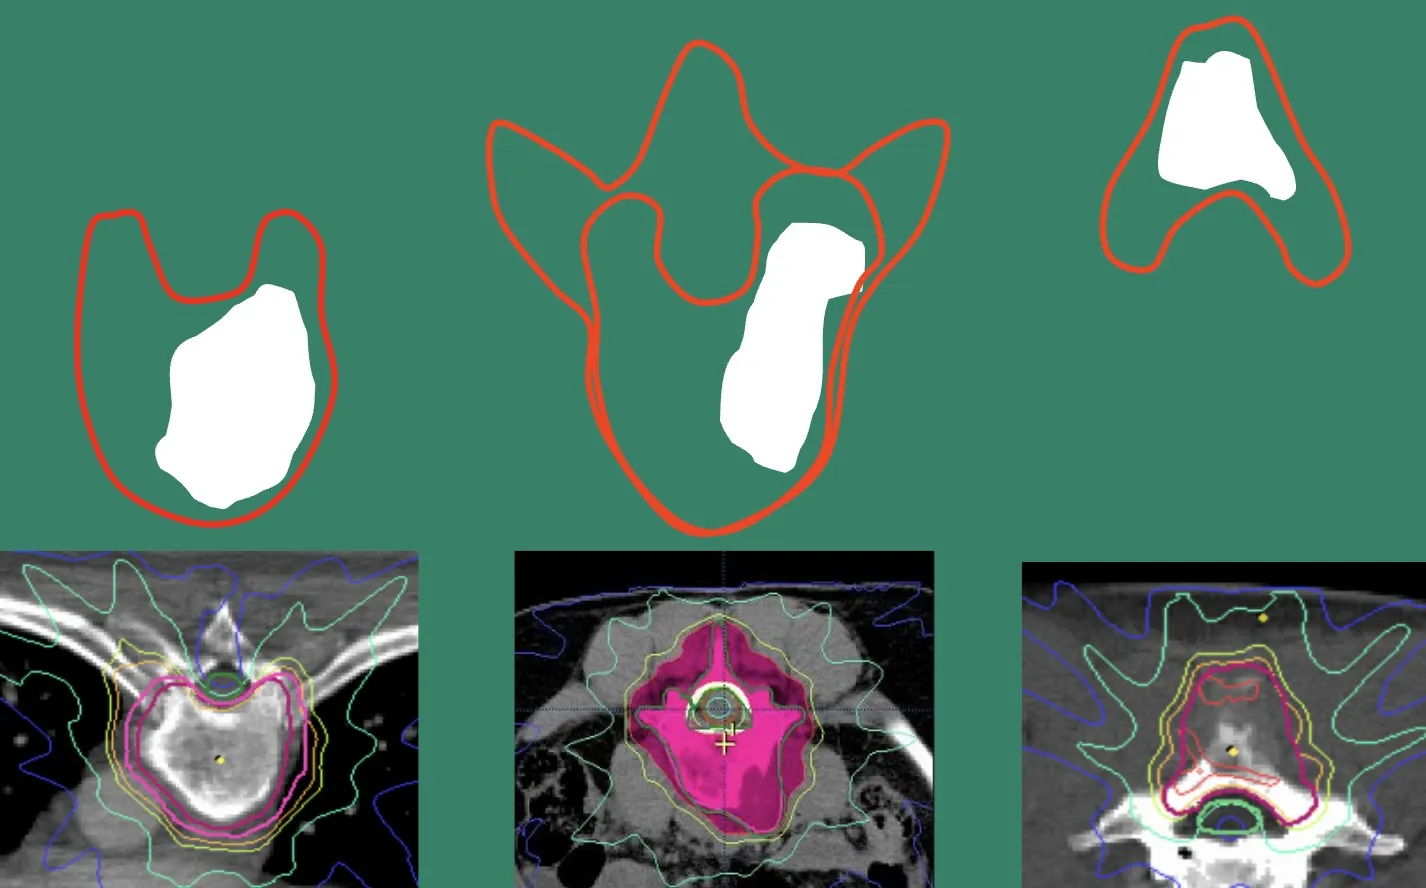

Junto a la cirugía y la quimioterapia, la radioterapia constituye la otra gran herramienta terapéutica, y en los últimos años ha experimentado un avance extraordinario. Existen tumores radiosensibles que responden de manera muy eficaz a este tratamiento, mientras que otros son más resistentes y requieren un abordaje combinado. Antes de indicar radioterapia, es esencial confirmar que la situación neurológica del paciente es estable y que no existe inestabilidad vertebral ni compresión medular, ya que en esos casos puede ser necesario intervenir primero para garantizar la seguridad del procedimiento. En determinados pacientes, especialmente cuando la cirugía no es viable por su estado general o por la extensión de la enfermedad, la radioterapia se convierte en la mejor opción paliativa, capaz de aliviar el dolor y mejorar la calidad de vida.

Es cierto que, en el caso de los tumores vertebrales metastásicos, la radioterapia moderna ha llegado a superar los resultados de las técnicas quirúrgicas tradicionales. En el pasado, la intervención más habitual consistía en realizar una laminectomía para descomprimir el sistema nervioso y aliviar los síntomas, pero hoy sabemos que la radioterapia puede lograr ese mismo efecto —y en muchos casos superarlo— de forma mucho menos invasiva. Los avances tecnológicos en los sistemas de planificación radioterápica son realmente notables: permiten concentrar dosis muy altas de radiación sobre el tumor y, al mismo tiempo, proteger completamente la médula espinal y los tejidos sanos circundantes. Gracias a ello, lesiones que antes no respondían bien a la radioterapia ahora pueden tratarse con gran precisión y eficacia. En definitiva, la radiosensibilidad de un tumor depende no solo de su tipo histológico, sino también de la cantidad de energía que puede concentrarse con seguridad sobre la lesión, algo que la tecnología actual ha hecho posible.

En los tumores malignos, cada vez con más frecuencia se valora la resección en bloque cuando es factible, junto con la corrección de la deformidad y la fijación necesaria para mantener la estabilidad vertebral. Además de la quimioterapia, la radioterapia desempeña un papel fundamental: en situaciones de compresión medular urgente, puede ser la primera medida terapéutica indicada desde el ámbito de Urgencias; con mayor frecuencia, se planifica como tratamiento coadyuvante de la cirugía, contribuyendo al control local del tumor y a la mejora de los síntomas.

Conviene destacar que, además de la radiocirugía, existen hoy técnicas de radioterapia fraccionada que permiten concentrar con gran precisión la dosis de energía sobre el tumor, evitando prácticamente la irradiación de estructuras sensibles como la médula espinal. Gracias a estos avances, la radioterapia está adquiriendo un papel cada vez más relevante, tanto como tratamiento principal en determinados casos, como terapia complementaria a la cirugía, y viceversa.